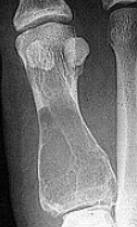

| Describe this lesion | A lytic lesion of the proximal phalanx that appears quite aggressive due to bone loss; however, the well-defined margins of the bone suggests a soft tissue tumor causing pressure atrophy against adjacent bone |